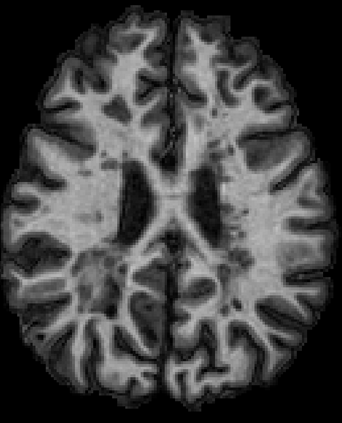

Recently, segmentation methods based on Convolutional Neural Networks (CNNs) showed promising performance in automatic Multiple Sclerosis (MS) lesions segmentation. These techniques have even outperformed human experts in controlled evaluation conditions such as Longitudinal MS Lesion Segmentation Challenge (ISBI Challenge). However state-of-the-art approaches trained to perform well on highly-controlled datasets fail to generalize on clinical data from unseen datasets. Instead of proposing another improvement of the segmentation accuracy, we propose a novel method robust to domain shift and performing well on unseen datasets, called DeepLesionBrain (DLB). This generalization property results from three main contributions. First, DLB is based on a large group of compact 3D CNNs. This spatially distributed strategy ensures a robust prediction despite the risk of generalization failure of some individual networks. Second, DLB includes a new image quality data augmentation to reduce dependency to training data specificity (e.g., acquisition protocol). Finally, to learn a more generalizable representation of MS lesions, we propose a hierarchical specialization learning (HSL). HSL is performed by pre-training a generic network over the whole brain, before using its weights as initialization to locally specialized networks. By this end, DLB learns both generic features extracted at global image level and specific features extracted at local image level. DLB generalization was validated in cross-dataset experiments on MSSEG'16, ISBI challenge, and in-house datasets. During experiments, DLB showed higher segmentation accuracy, better segmentation consistency and greater generalization performance compared to state-of-the-art methods. Therefore, DLB offers a robust framework well-suited for clinical practice.